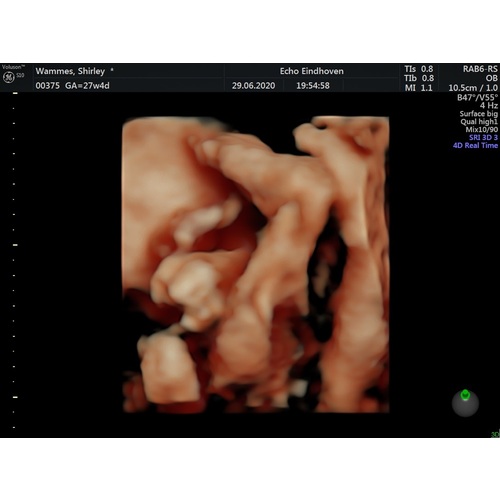

Hier ligt ze met haar gezicht naar mijn rug te kijken. Inderdaad armen en benen ervoor. Kontje naar beneden. Gister 3/4d echo gehad. Het duurde even. Hebben een paar keer het snoetje gezien maar niet duidelijk!